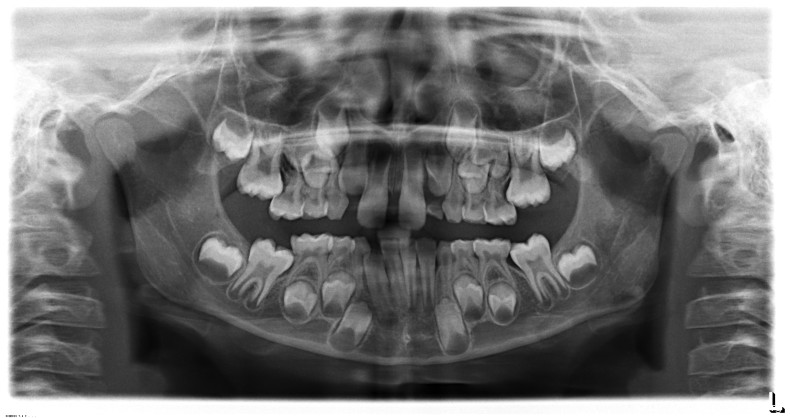

Der Besonderheit der unterminierenden Resorption, meist der Milchfünfer durch die bleibenden 6er (Abb. 5) oder der Milchzweier durch die bleibenden 1er (Abb. 6 – mit häufiger Folge, dass die bleibenden 2er dann die Milchdreier resorbieren), sollte auch Beachtung geschenkt werden. Beides steht für ein Mangelwachstum der Kiefer und sollte frühzeitig therapiert werden, um die spätere Extraktion von bleibenden Zähnen zu verhindern.